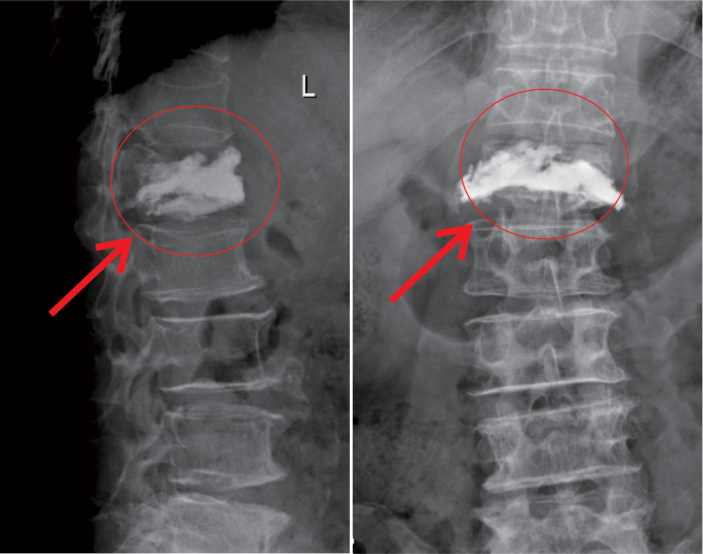

△術前MR顯示,第一腰椎壓縮性骨折

△術後,病變的椎體迅速恢複了功能